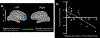

The gut microbiota affects many important host functions, including the immune response and the nervous system1. However, while substantial progress has been made in growing diverse microorganisms of the microbiota2, 23-65% of species residing in the human gut remain uncultured3,4, which is an obstacle for understanding their biological roles. A likely reason for this unculturability is the absence in artificial media of key growth factors that are provided by neighbouring bacteria in situ5,6. In the present study, we used co-culture to isolate KLE1738, which required the presence of Bacteroides fragilis to grow. Bioassay-driven purification of B. fragilis supernatant led to the isolation of the growth factor, which, surprisingly, is the major inhibitory neurotransmitter GABA (γ-aminobutyric acid). GABA was the only tested nutrient that supported the growth of KLE1738, and a genome analysis supported a GABA-dependent metabolism mechanism. Using growth of KLE1738 as an indicator, we isolated a variety of GABA-producing bacteria, and found that Bacteroides ssp. produced large quantities of GABA. Genome-based metabolic modelling of the human gut microbiota revealed multiple genera with the predicted capability to produce or consume GABA. A transcriptome analysis of human stool samples from healthy individuals showed that GABA-producing pathways are actively expressed by Bacteroides, Parabacteroides and Escherichia species. By coupling 16S ribosmal RNA sequencing with functional magentic resonance imaging in patients with major depressive disorder, a disease associated with an altered GABA-mediated response, we found that the relative abundance levels of faecal Bacteroides are negatively correlated with brain signatures associated with depression.